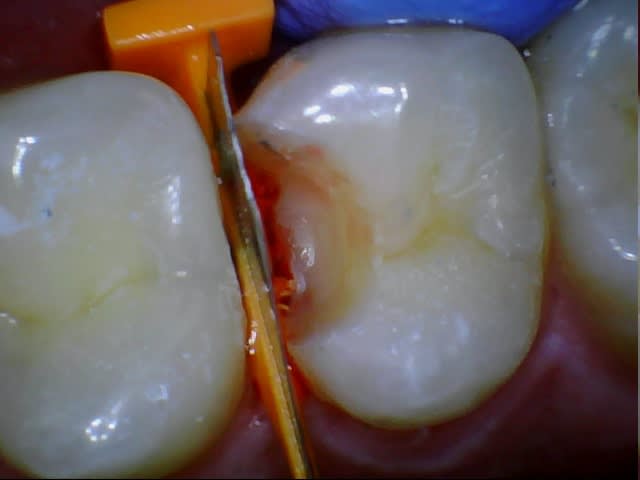

eMax de ce soir.

Collage automordançant G-Cem.

Bah voilà un argument de plus pour la levée de l'opposabilité pour les composites. Alors ameli? Qu'est qui favorise le plus l'accès au soins? Cet onaly qui doit coûter entre 300 et 500€ ou un compo à 150€ qui, collé dans les même conditions, aurait un pronostic équivalent?

(Il ne s'agit pas d'une critique de confrère, je prèfère cent fois quelqu'un qui soigne une carie comme ça qu'un autre qui foule 2 couches de compo sans digue)

Je trouve que c'est un patient qui devrait avoir des soins paro et des compo, pas des e-max. Et j'aime pas le collage au G-cem, en fait c'est le point faible de ton traitement, et c'est si facile de coller ce cas avec le total etch.

On peut penser qu'Arnaud aura vu le tartre sous-gingival et fait le nécessaire, mais pourquoi pas d'emax et plutôt des compos? Rapport à la taille des cavités? A l'hygiène pas top?

Oui rapport à la taille de la cavité. J'ai pas dit que c'était moins bien de faire un emax plutôt qu'un compo, je dis juste que c'est plus coûteux pour un bénéfice médical proche de zéro. Mais évidement si on veut faire un compo qui peut rivaliser avec cet onlay il faudra palper un pru plus que 28,92.

Il y a une équivalence thérapeutique entre les deux solutions tant que la forme de la préparation ne nécessite pas de délabrement, et bien que l'arsenal à mettre en œuvre est bien plus important pour l'inlay, je préfère de l'eMax dans ma bouche (et un peu de joint résine) qu'un compo.

Donc je choisis la solution où le patient est aussi bien soigné et où je ne sors pas du pognon de ma poche quand je le soigne.